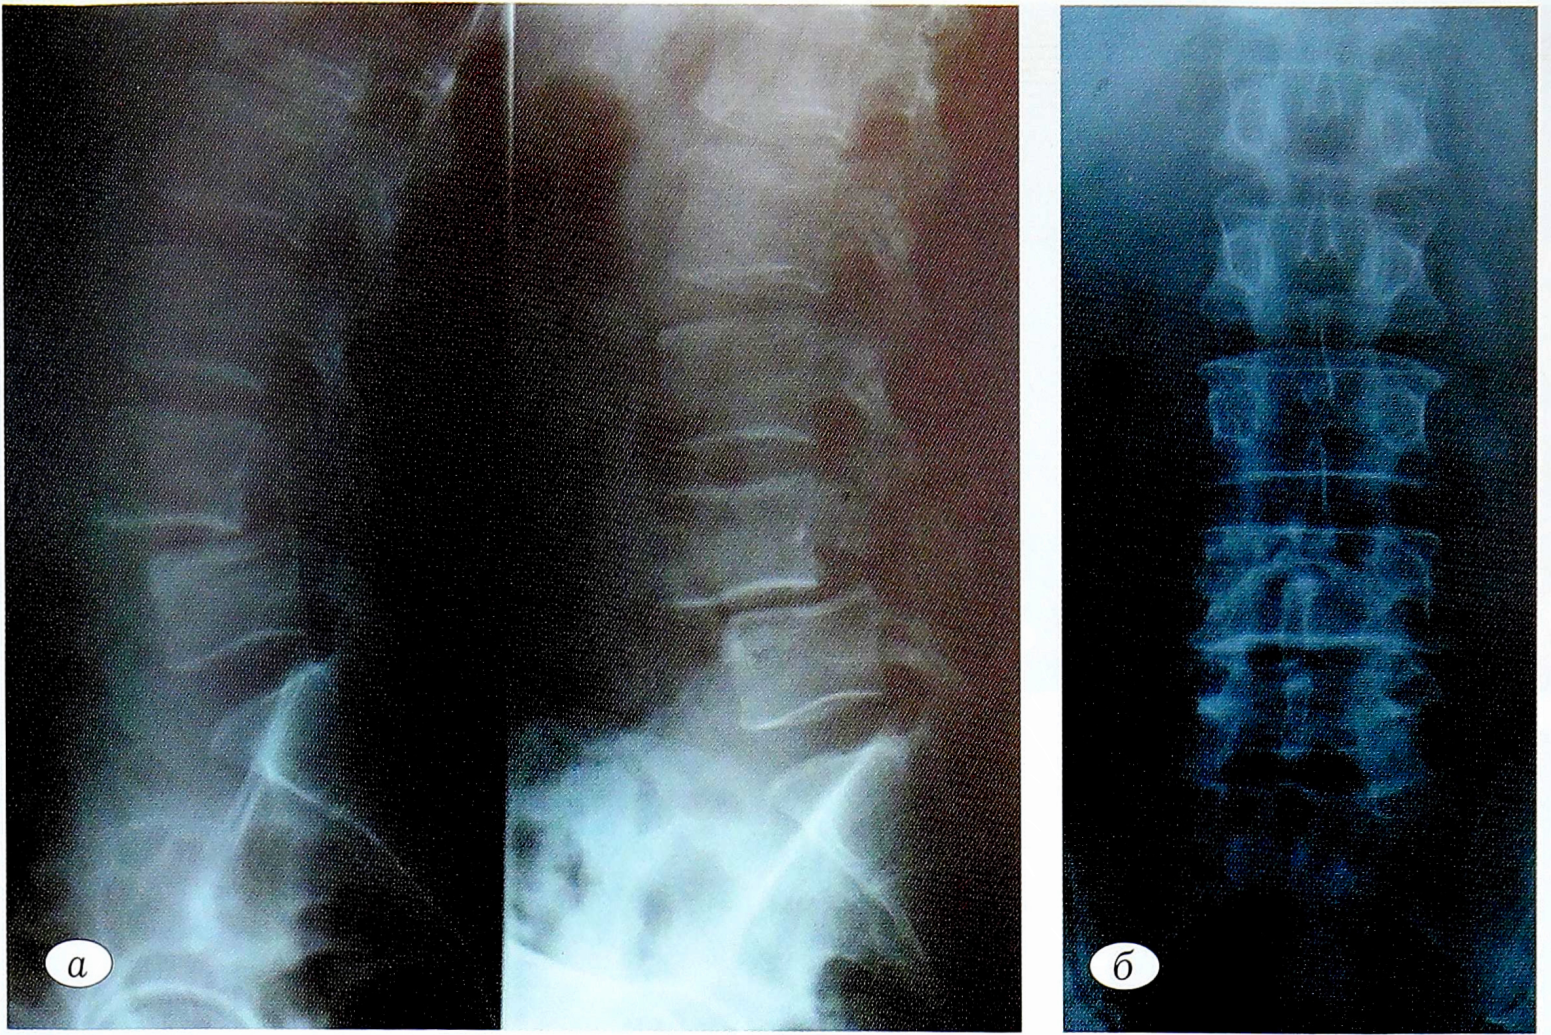

Поясничная спондилография в прямой проекции и с функциональными пробами (рис. 2, а, б): остеохондроз, спондилоартроз, нестабильный антеспондилолистез позвонка II стадии со спондилолизом справа.

Рис. 2. Спондилография поясничного отдела позвоночника пациента Ш. с функциональными пробами: а — боковые проекции, б — прямая проекция.

Fig. 2. Spondylography of the lumbar spine of patient S. with functional samples: a —lateral projections, b — direct projection.